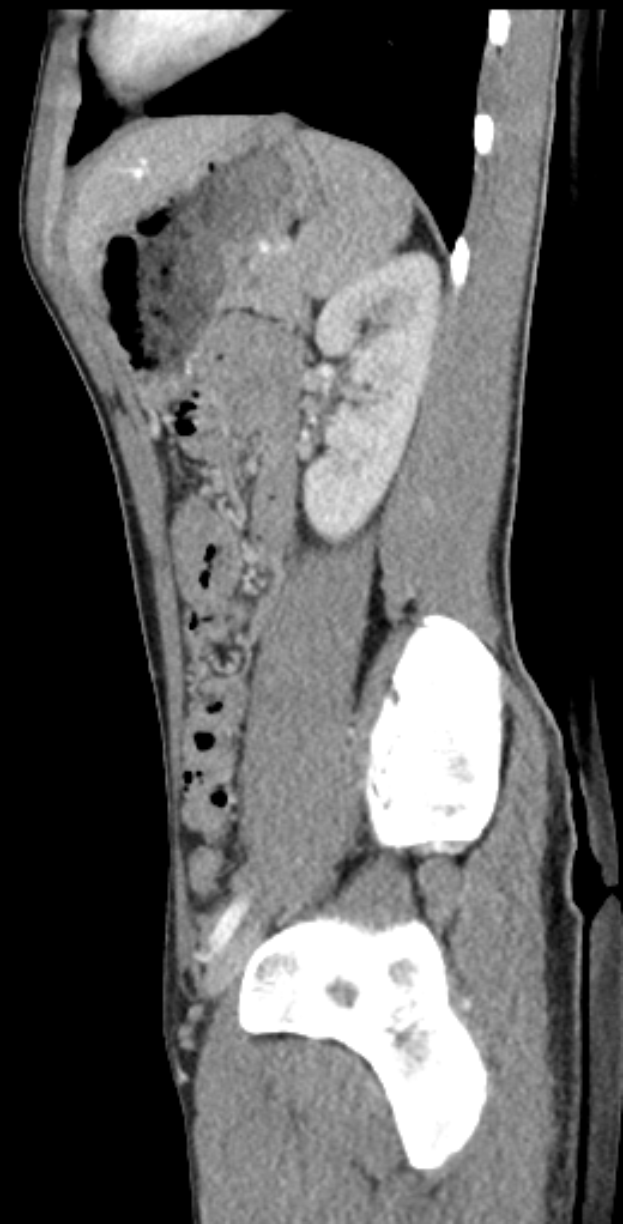

Eine MRT-Aufnahme eines Knies, die einen Riss in der Mitte zeigt, umgeben von einem dunklen Hintergrund.Isabella Reinhardt

Muskelverletzungen: Köln vorübergehend ohne Thielmann und Sebulonsen - Doppelter Verletzungsrückschlag beim 1. FC Köln nach Hoffenheim-Remis

Der 1. FC Köln hat nach dem 2:2 gegen die TSG Hoffenheim zwei Leistungsträger mit Muskelverletzungen verloren. Sowohl Jan Thielmann als auch Sebastian Sebulonsen fallen aus und hinterlassen frühzeitige Lücken in der Startelf.